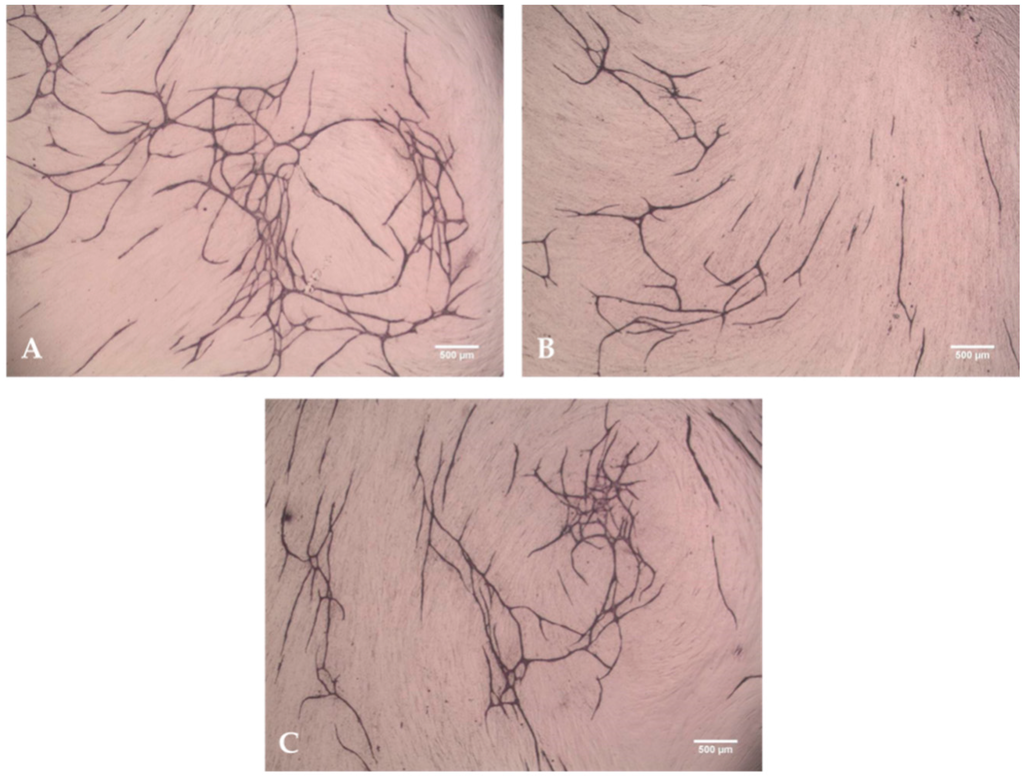

2.3. Angiogenesis Assay with Functionalized Titanium Implants

2.4. Angiogenesis Assay with Cytokines HMGB1 and VEGF